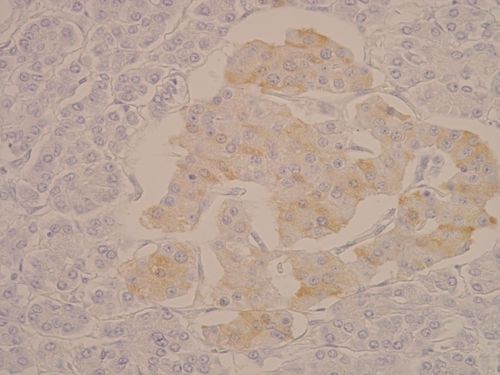

Islet of Langerhans - detail (immunohistochemical evidence of C - peptide in beta cells)[edit | edit source]

Description: Beta cells are in the center of the islet (produce insulin), alpha cells (produce glucagon) and delta cells (produce somatostatin) are peripheral.

note: C-peptide (colored golden) is produced during the release of insulin into the blood (by splicing the insulin polypeptide chain), so it is a product of the beta cells of the islets of Langerhans.